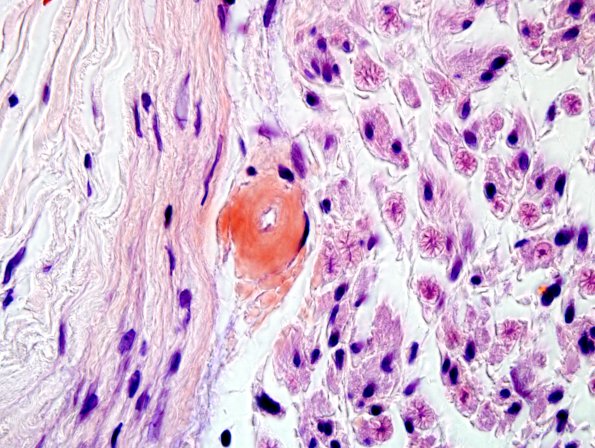

4C2,3A,B Additional capillary and venules are strongly reactive for Congo Red. (Congo Red)